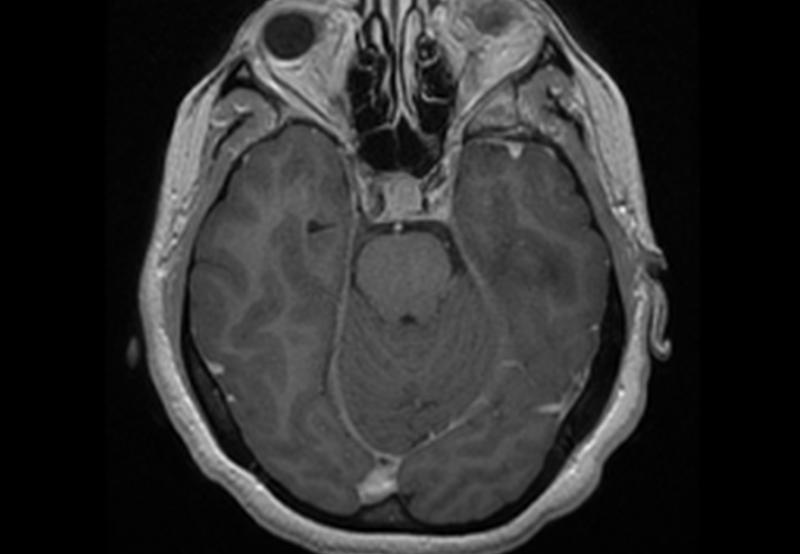

Clásicamente se describe como una alteración en la producción, circulación o drenaje del líquido cefalorraquídeo. Existen múltiples causas que pueden originar este fenómeno y deben ser ágilmente identificados para su oportuno tratamiento ya que puede poner el riesgo la salud y la vida.

El tratamiento es inminentemente quirúrgico, a través de la colocación de un sistéma de derivación o utilizando técnicas endoscópicas.